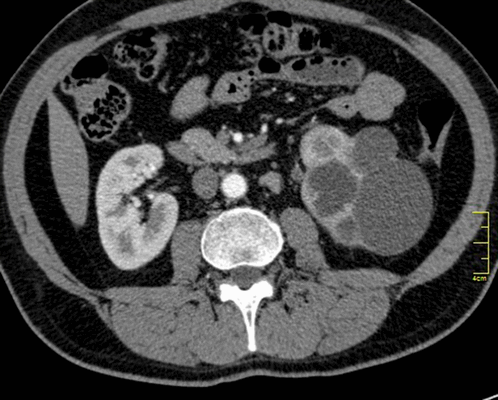

Палочка Коха, вызывающая туберкулез, может быть обнаружена в разных мягкотканных органах (печени, почках, мозге и др.) и костных структурах. Только при комплексной диагностике проводят дифференциацию патологии от других заболеваний, определяют степень, локализацию и тяжесть патологического процесса.

Туберкулез почки

- милиарный туберкулез характеризуется множественными очагами поражения (до 2 мм), локализованными во всех сегментах легких, часто обнаруживают патологии в печени, почках, кишечнике, селезенке, мозге, костях. Данный вид заболевания имеет неблагоприятный прогноз и высокую скорость прогрессии. Поэтому важна ранняя диагностика.